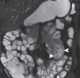

Small bowel hamartoma